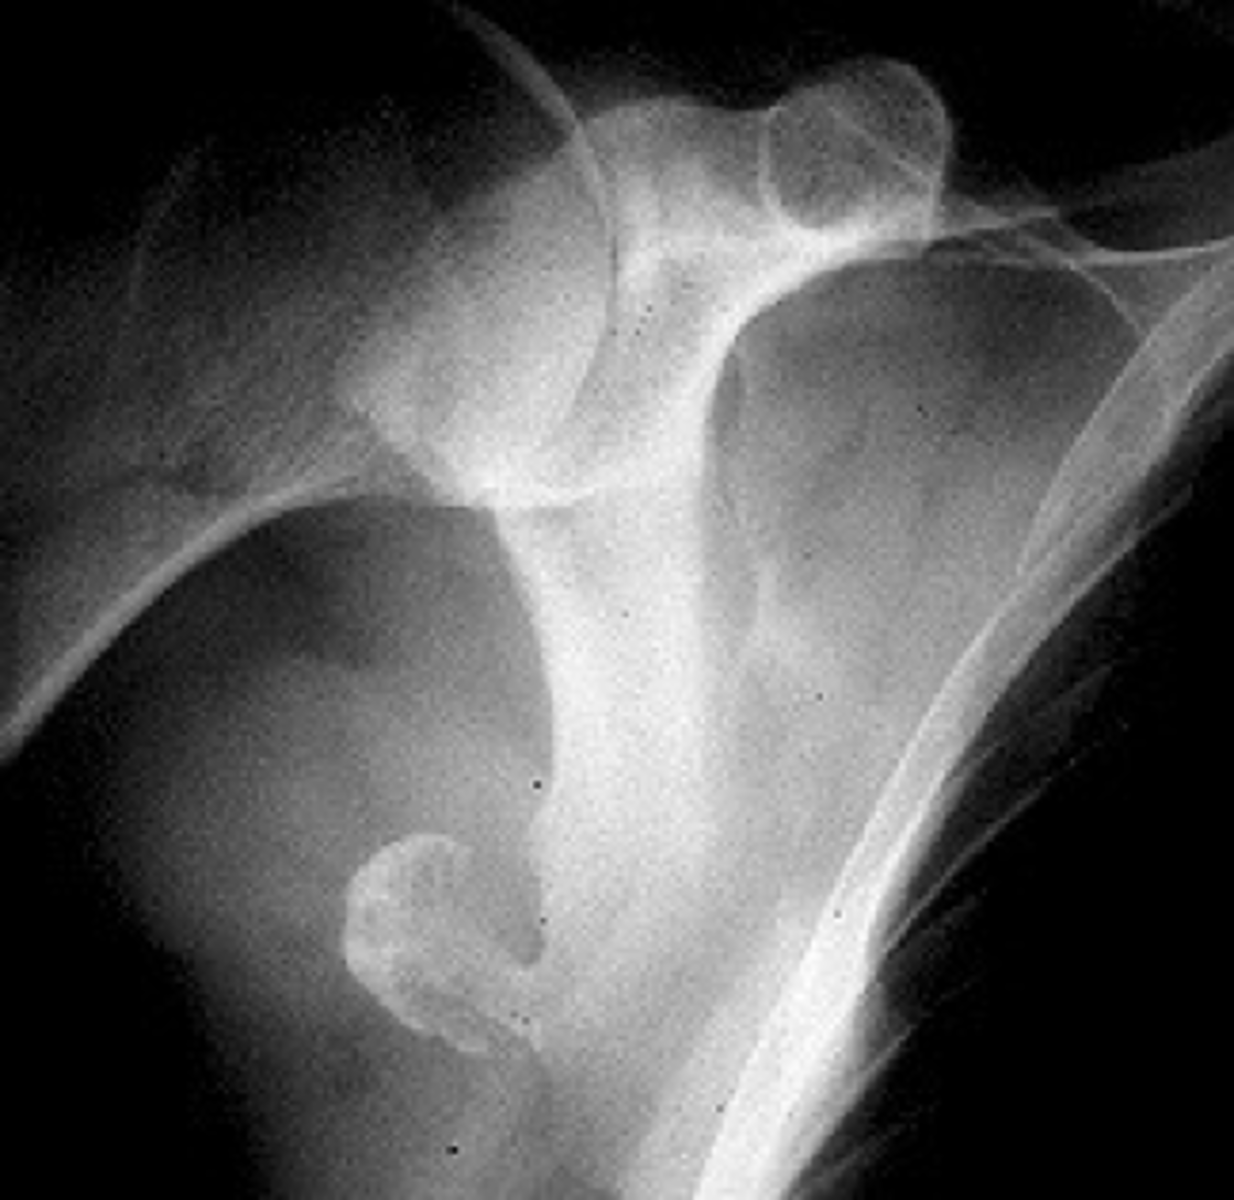

Solitary osteochondroma

- Most common benign skeletal growth or tumor

- 50% of all benign bone tumors

- 10-15% of all primary bone tumors

- 75% <20 y.o.

- M:F, 2:1

- Malignant transformation <1%

<p>- Most common benign skeletal growth or tumor</p><p>- 50% of all benign bone tumors</p><p>- 10-15% of all primary bone tumors</p><p>- 75% &lt;20 y.o.</p><p>- M:F, 2:1</p><p>- Malignant transformation &lt;1%</p>

- Mostly asymptomatic

- Painless, hard mass

- Stalk may fracture

- Pain and rapid growth = malignant transformation

State the clinical features of solitary osteochondroma

Pedunculated

_____ solitary osteochondroma:

- Metaphyseal

- Thin, elongated stalk

- Cortex and medulla continuous

- Calcified cap

- Projects away from joint

- Lucent when en face (on end)

<p>_____ solitary osteochondroma:</p><p>- Metaphyseal</p><p>- Thin, elongated stalk</p><p>- Cortex and medulla continuous</p><p>- Calcified cap</p><p>- Projects away from joint</p><p>- Lucent when en face (on end)</p>

Sessile

- Broad-based

- Wide, broad metaphysis

- Cartilage cap uncommon

<p>_____ solitary osteochondroma:</p><p>- Broad-based</p><p>- Metaphyseal</p><p>- Wide, broad metaphysis</p><p>- Lucent when en face (on end)</p><p>- Cartilage cap uncommon</p>